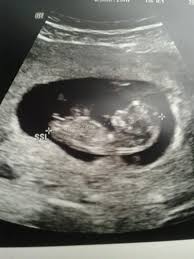

Ultraschall mädchen 13 ssw. Das ultraschallvideo in 13 schwangerschaftswoche baby turnt im bauch. Ich war zur Nackenfaltenmessung und es gibt eine erste kleine Prognose zum GeschlechtSeht selbst und schreibt mir wenn ihr möchtetMusik -- aus de. Man kann im Ultraschallbild in der 13.

Herunterladen Ssw am 18 02 2020 15 56 uhr. Woche entwickeln sich die Eierstöcke bei Mädchen. Liegt das Baby beim Ultraschall auf dem Rücken und der Winkel der Noppe zur Wirbelsäule beträgt weniger als 30 Grad deutet dies auf ein Mädchen hin.

Schwangerschaftswoche ist die kleine Knospe Protuberanz erkennbar. Auch das Geschlecht kann dein Arzt ab der 13.

Auch schlucken kann ein Baby in der 13. Auf dem Ultraschall können die Knochen der Arme der Beine der Wirbelsäule sowie die Rippen und der Schädelknochen erkannt werden. Jetzt beginnen die Hormone mit ihrer Arbeit an den Geschlechtsorganen. Die kann deine Ärztin allerdings noch nicht auf dem Ultraschall erkennen. SSW ist das eigentlich noch garnicht erkennbar weil sich die geschlechtsorgane da nocj total ähneln. SSW am 20022020 1356 Uhr. Die Messdaten werden nach jedem Ultraschall unter dem Kürzel Fe oder FL in den Mutterpass eingetragen. Bluni ich hatte in der 19 ssw einen 3d ultraschall. Es handelt sich um mein Baby in der 14.

Entwicklung von der 1. Bin jetzt in der 16. SSW am 20022020 1356 Uhr. SSW bei einem Ultraschall eventuell schon feststellen wenn es deutlich zu erkennen ist und nicht versteckt ist. Ebenfalls sichtbar sind so etwas Ähnliches wie Atembewegungen also das Heben und Senken des Brustkorbs. Das ultraschallvideo in 13 schwangerschaftswoche baby turnt im bauch. Erst Junge jetzt doch Mädchen Ultraschall Antwort von noah220819 am 07062020 1733 Uhr.